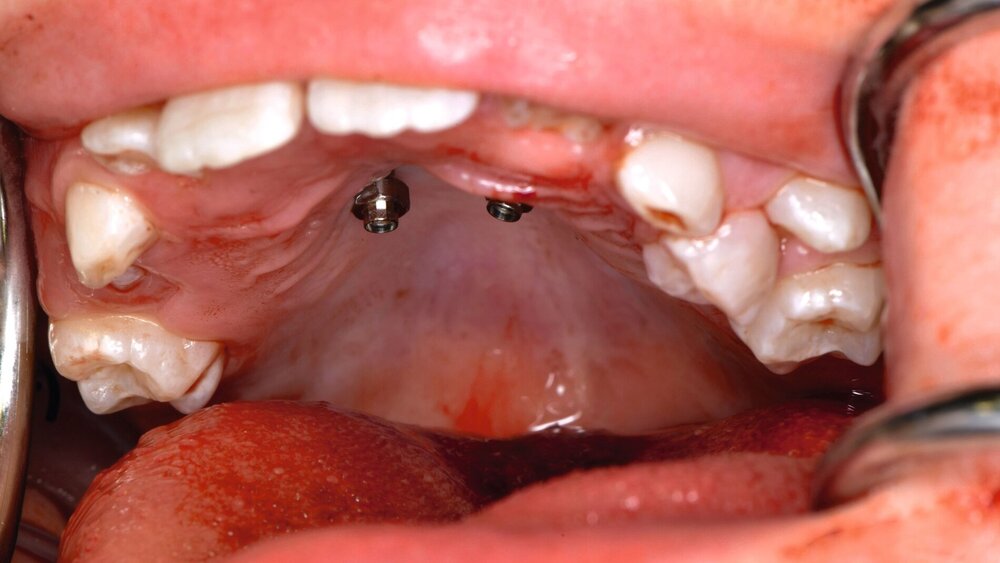

Die Zähne 36, 37, 46 und 47 wurden in Allgemeinanästhesie chirurgisch freigelegt. Zusätzlich wurden die beiden paramedianen Mini-Implantate (2 x 9 mm, Benefit System; PSM North America, Indio, CA) ohne Vorbohren mithilfe der zuvor hergestellten Schablone inseriert (Abbildung 3). Für die Platzierung der Mini-Implantate wurde ein Winkelschraubendreher verwendet. Direkt nach der Operation wurde die bmx DIRECT Hyrax-Schraube (10 mm, BENEfit®-System, Dentalline, Birkenfeld, Deutschland) an den Mini-Implantaten befestigt, um ein MARPE zu erzielen (Abbildung 4).